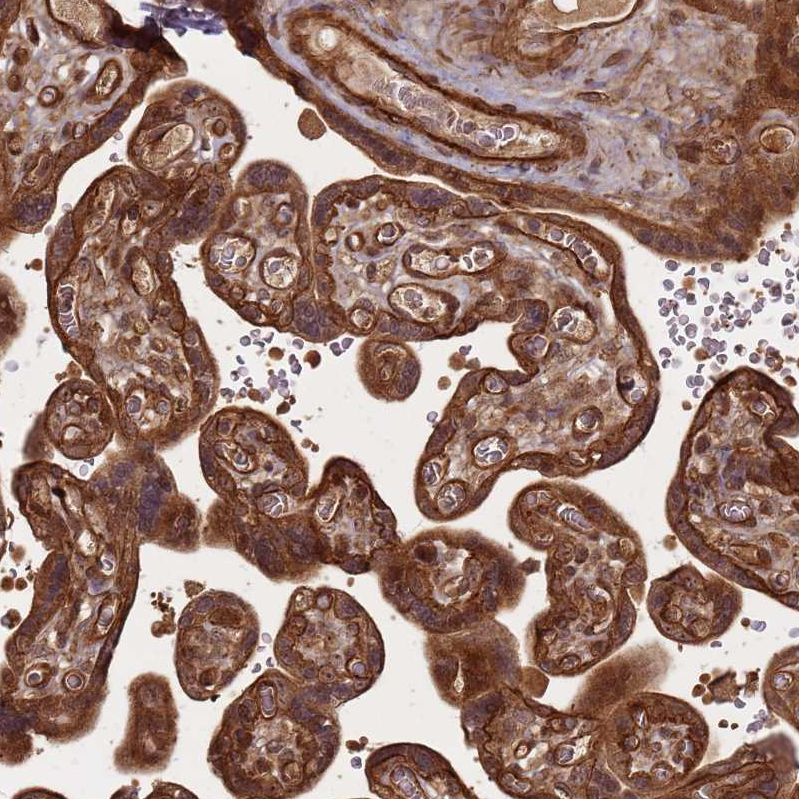

Immunohistochemical staining of human placenta shows strong cytoplasmic positivity in trophoblastic cells and endothelial cells.